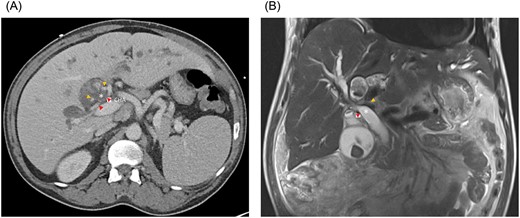

A 51-year-old male presented with abdominal pain, jaundice and fever. His medical history was significant for type 2 diabetes mellitus and dyslipidemia. He had no history of liver disease, pancreatitis or hepatobiliary surgery. He had a cholestatic elevation of liver enzymes with a total bilirubin of 17.6 mg/dL and alkaline phosphatase of 508 IU/L. Computed tomography (CT) showed intrahepatic biliary dilatation and large stones within the left intrahepatic bile duct (Fig. 1A). The common bile duct was dilated to 18 mm and there was a stone at the ampulla. Magnetic resonance imaging (MRI) demonstrated bilateral hepatolithiasis and a focal CHD stricture near its bifurcation (Fig. 1B).

(A) Axial CT and (B) coronal MRI imaging showing the right anterior (orange arrowheads) and right posterior (red arrowheads) hepatic arteries encircling the common hepatic duct (white asterisk). CHA, common hepatic artery.

At laparotomy, we identified an early bifurcation of the RHA into its anterior and posterior branches, immediately distal to the branching of the left hepatic artery. The right anterior artery crossed anterior to the CHD, whereas the right posterior artery coursed posterior to the CHD (Fig. 1A and B). These arterial branches were densely adherent to the CHD, and were circumferentially constricting the CHD. After completing a cholecystectomy, we performed an arterial divestment, dissecting in the periadventitial plane along the course of the RHA, to release the anterior and posterior RHA branches from the CHD (Fig. 2A and B). Intraoperative ultrasound confirmed extensive hepatolithiasis, predominantly in the left hepatic duct. We transected the CHD 1 cm distal to its bifurcation and transposed the anterior RHA branch posterior to the CHD. We used Spyglass™ Discover Digital Catheter (Boston Scientific, Natick, MA) direct cholangioscopy to guide clearance of the hepatolithiasis. Intrahepatic stones were extracted using stone forceps and biliary Fogarty catheters. Cholangioscopy revealed no intrahepatic strictures and normal appearance of the biliary epithelium. The CHD was reconstructed in an end-to-end fashion over bilateral plastic biliary stents. Histological evaluation of the gallbladder revealed chronic cholecystitis and a segment 4B liver biopsy showed changes consistent with chronic cholestasis. The patient had an uneventful postoperative course and has remained asymptomatic after 3 months of follow-up.